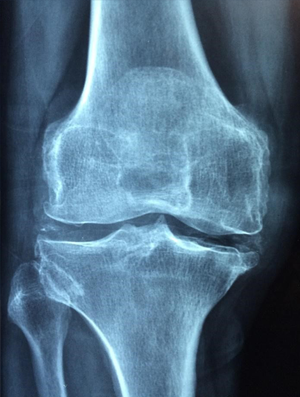

Arthritis can cause chronic inflammation, pain, and stiffness in the joints of the body such as the fingers, hands, knees, elbows, hips, jaw. ACV Helps with Osteoarthritis, Rheumatoid arthritis, Gout, Psoriatic arthritis and more.